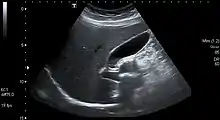

کیسه صفرا اندام توخالی است که در گودی کم عمق زیر لوب راست کبد قرار دارد.[3] در بزرگسالان، کیسه صفرا تقریباً ۷ تا ۱۰ سانتیمتر (۲٫۸ تا ۳٫۹ اینچ) طول و به ۴ سانتیمتر (۱٫۶ اینچ) قطر دارد.۷ تا ۱۰ سانتیمتر (۲٫۸ تا ۳٫۹ اینچ) کیسه صفرا حدود ۵۰ میلیلیتر (۱٫۸ اونس) حجم دارد.[3]

کیسهٔ صفرا گلابیشکل است و نوک آن به مجرای کیستیک باز میشود.[4] کیسهٔ صفرا به سه بخش انتهایی، بدنه و گردن تقسیم میشود. بخش انتهایی یک پایهٔ گرد است، به صورت زاویهدار به طوری که با دیوارهٔ شکم روبرو است. بدنه در گودی در سطح کبد تحتانی قرار دارد.[5]